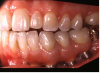

(13.) Prosthetic design allowing access to FMG interface.

Figure 13

(14.) Healthy Gingival Tissue.

Figure 14

(15.) FMG access and convex intaglio profile.

Figure 15

(16.) FMG access and convex intaglio profile.

Figure 16

Many factors should be considered when designing implant-supported restorations to reduce the risk of peri-implantitis affecting physical removal of bacterial plaque at the FMG. Included are oral hygiene devices, accessibility, prosthetic shapes, and patient ability to comply with oral hygiene procedures. The design should be conveniently hygienic so patients can easily comply with the recommended oral hygiene procedures. Physical removal of bacterial plaque on the intaglio surface at and above the FMG reduces the risk of peri-implantitis in the sub-gingival transmucosal tissue around dental implants. The original fixed prosthetic design presented by Branemark, a "High water design", provided access to all surfaces for oral hygiene management without a patient complaint of food accumulation (Figure 9 and Figure 10). Notably, relief above the gingiva was not patient complaint with this design. Lack of embrasure access to the FMG and intaglio surfaces for oral hygiene management can lead to peri-implantitis (Figure 11 and Figure 12). Stein recommended a convex modified ridgelap pontic design with lingual and palatal access to facilitate plaque removal from the intaglio surface under pontics in fixed prosthetics with dental floss.20 These shapes should be standard for fixed implant-supported restorations whether individual or multi-unit restorations made of ceramo-metal or milled zirconia (Figure 13 through Figure 16).